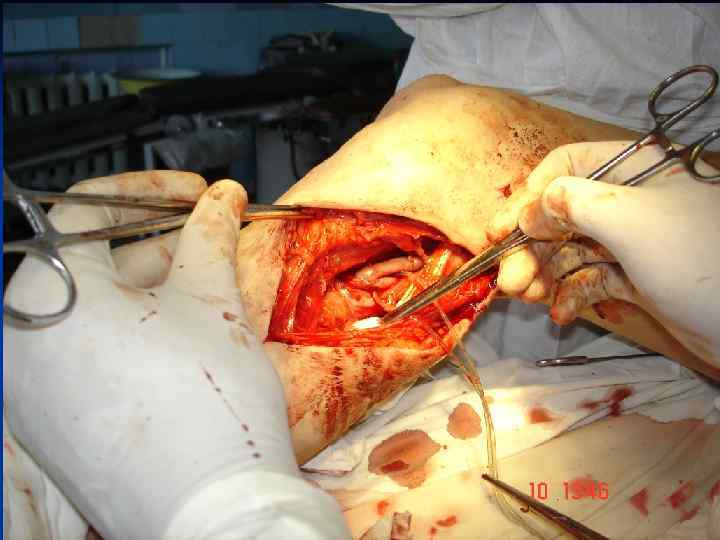

Стегно-підколінне аутовенозне протезування

Стегно-підколінне аутовенозне протезування